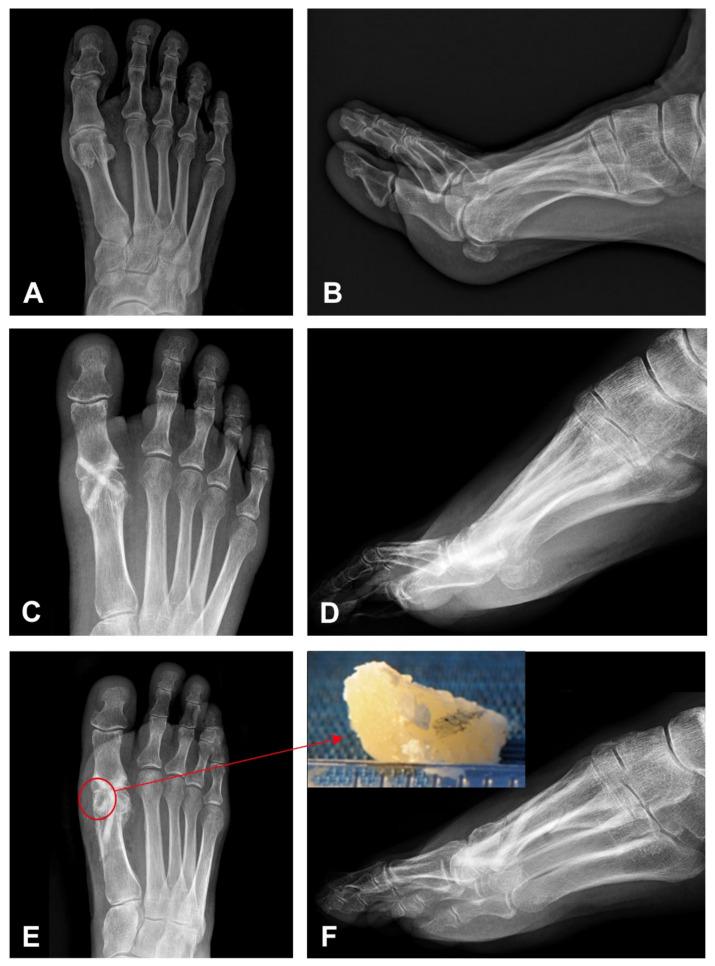

Hallux rigidus is degenerative arthritis of the first metatarsophalangeal joint characterized by pain and stiffness in the joint with limitation of motion and functional impairment. Recently, bone grafts have been introduced in orthopedic procedures, namely osteosynthesis and arthrodesis. Allografts can induce bone formation, provide support for vascular and bone ingrowth and have a low risk of immunological rejection. A 52-year-old female patient with hallux rigidus underwent arthrodesis of the first metatarsophalangeal joint using Shark Screw made of allogenic cortical bone. Corrective surgery was performed after 10 weeks, and a 5 × 3 mm large part of the Shark Screw with the surrounding patient's bone was removed. A histological evaluation revealed a vascularized graft with the newly formed compact lamellar bone fitting exactly to the cortical graft. The bone surface was lined by plump osteoblasts with osteoid production, and osteocytes were present in the lacunae. The arthrodesis of the first metatarsophalangeal joint using an allogenic cortical bone graft results in fast, primary bone healing without immunological rejection. This case suggests that the cortical allograft is a good and safe treatment option with an excellent graft incorporation into the host bone. However, as the literature evaluating the histology of different bone grafts is scarce, further high-level evidence studies with adequate sample sizes are needed to confirm our findings.

拇僵硬症是第一跖趾关节的退行性关节炎,其特征为关节疼痛、僵硬,伴有活动受限和功能障碍。最近,骨移植已被引入骨科手术,即骨固定术和关节融合术。同种异体骨移植可诱导骨形成,为血管和骨长入提供支撑,且免疫排斥风险低。一名52岁患有拇僵硬症的女性患者接受了使用同种异体皮质骨制成的鲨鱼钉进行的第一跖趾关节融合术。10周后进行了矫正手术,取出了一块5×3毫米大小的带有周围患者骨组织的鲨鱼钉。组织学评估显示,移植骨有血管化,新形成的致密板层骨与皮质移植骨精确匹配。骨表面衬有产生类骨质的丰满成骨细胞,骨陷窝中有骨细胞。使用同种异体皮质骨移植进行第一跖趾关节融合术可实现快速的一期骨愈合,且无免疫排斥反应。该病例表明,皮质同种异体骨移植是一种良好且安全的治疗选择,移植骨与宿主骨的融合效果极佳。然而,由于评估不同骨移植组织学的文献较少,需要进一步开展样本量充足的高水平证据研究来证实我们的发现。